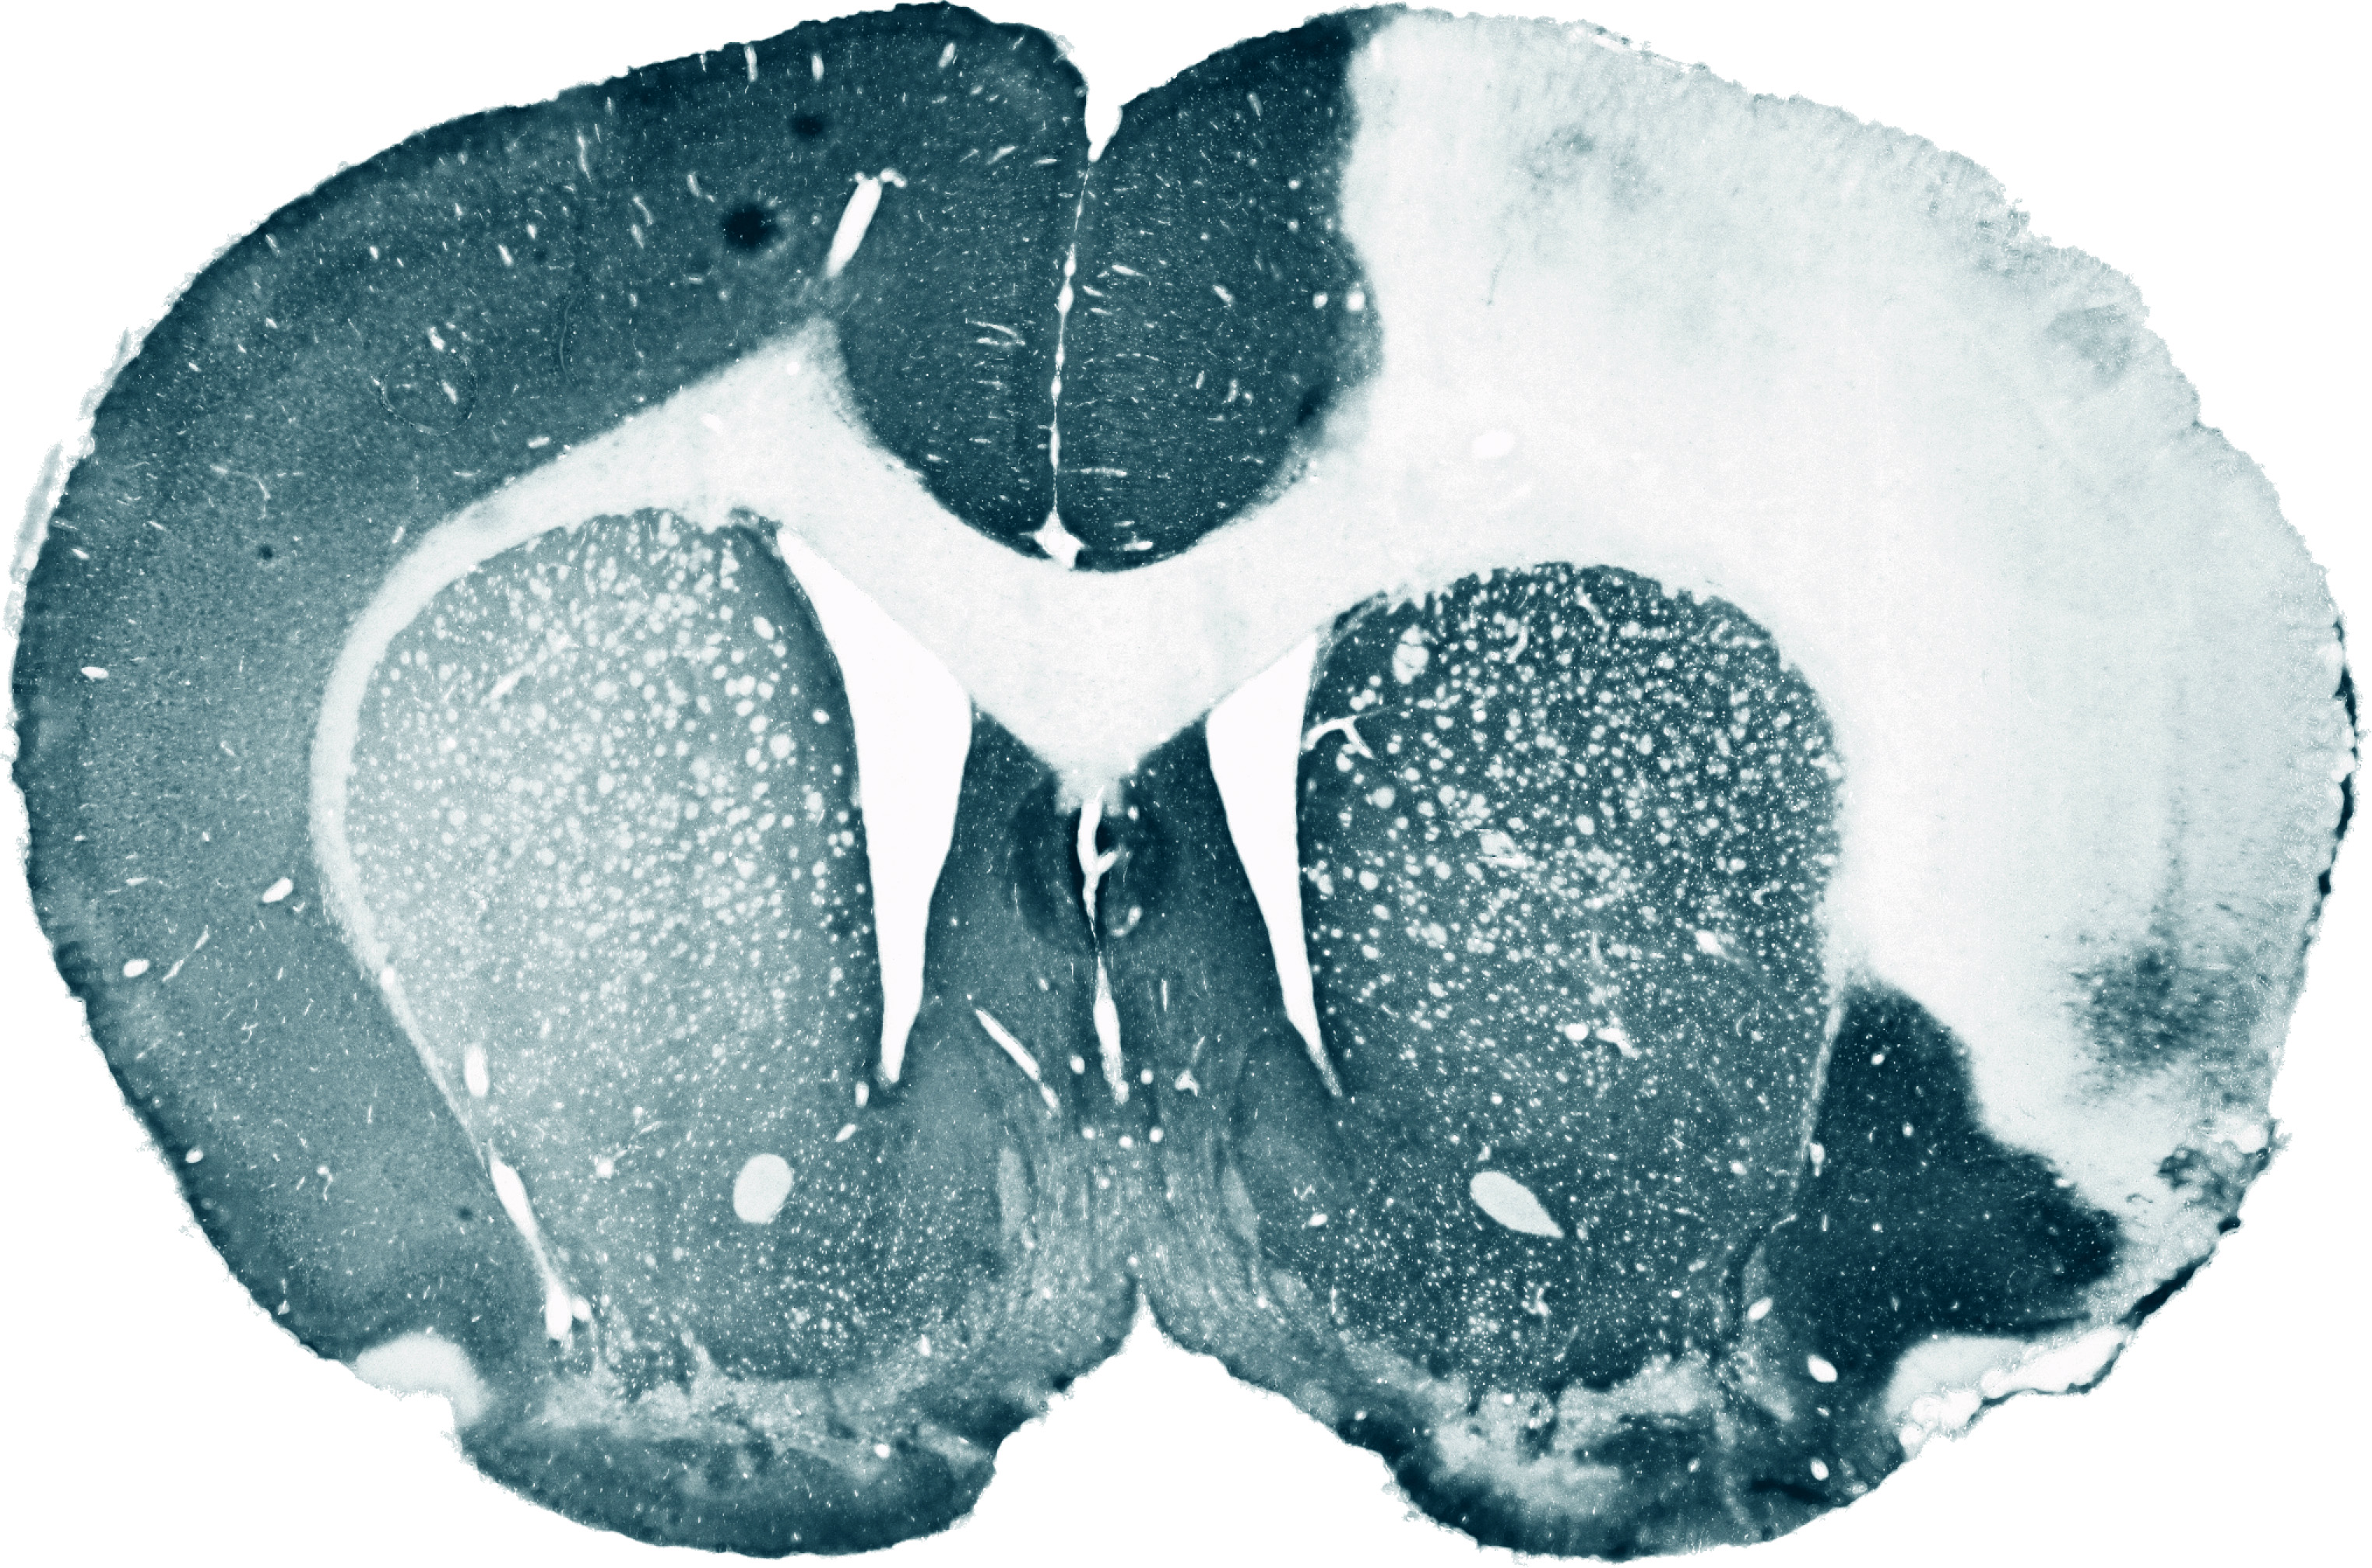

Eine Schlüsselrolle bei der Stammzelltherapie übernehmen die mit besonderen immunologischen Eigenschaften ausgestatteten und daher bei Transplantationen als besonders geeignet geltenden mesenchymalen Stammzellen (MSC). Auf ihre herausragende Bedeutung bei der Behandlung akuter Erkrankungen wie Herzinfarkt oder Schlaganfall wurde in präklinischen Studien bereits mehrfach hingewiesen. Weiterhin wurde gezeigt, dass mesenchymale Stammzellen nach einem Schlaganfall in kleinen Mengen zielgerichtet zu den betroffenen Hirnarealen wandern. Dort lagern sie für den späteren Übertritt in das dahinter liegende geschädigte Gewebe aktiv an das Endothel eines Gefäßes an. Dieser als "Homing" bezeichnete Prozess wird durch verschiedene komplementäre molekulare Strukturen vermittelt.

Der Fokus der Leipziger Forschungsgruppe richtet sich sowohl auf den Nachweis des Therapieeffekts des Homings bei Schlaganfall als auch auf die Optimierung des Homing-Prozesses. "Die meisten mesenchymalen Stammzellen werden nach systemischer Applikation in den feinen Kapillaren der Lungen aus dem Blutkreislauf herausgefiltert", erläutert Boltze. Daher wird nun untersucht, wie die Zellen molekularbiologisch modifiziert werden können, damit sie nicht nur näher, sondern vor allem in größerer Anzahl zum Herd des Schlaganfalls gelangen. Dafür werden sie mit einem Rezeptor für ein Oberflächenmolekül versehen, das insbesondere in Gefäßstrombahnen nahe dem Schlaganfall vorkommt. "Diese Kombination wirkt wie eine Art Leim, der für ein besseres Anhaften an den Endothelzellen sorgt", so der Arzt und Neurobiologe weiter.